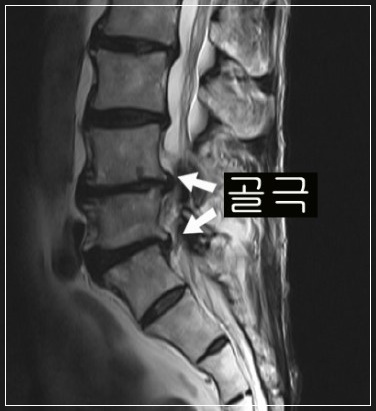

건강보험심사평가원 통계에 따르면, 2017년 척추관협착증 환자 수는 154여만 명에 달합니다. 척추관협착증은 척추 뼈 사이 추간공이 퇴행성 변화 혹은 다른 질환으로 인해 좁아지면서 척추 신경을 눌러 생기는 질환입니다 중년 이후에 많이 나타나는 흔한 질환의 하나로 말 그대로 신경이 지나가는 공간인 척추관이 좁아져서 신경을 누르는 병입니다.

척추관 협착증에서는 주로 뼈, 관절과 같은 딱딱한 조직이 신경을 누릅니다. 통증의 양상을 보면, 허리 디스크는 빠른 시간 내에 진행하는 경우가 많고 척추관 협착증은 오랜 시간에 걸쳐 서서히 나타나는 경우가 많습니다. 또한 척추관 협착증의 특징적인 증상으로 간헐적 파행이 있습니다. 이는 허리 디스크의 증상과 구별되는 것으로 앉아 있을 때는 괜찮은데 조금만 걸어도 다리가 저리고 아파서 앉아 쉬었다가 다시 걸어야 하는 보행 장애 증상을 말합니다.